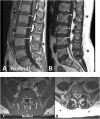

Case presentation: A 51-year-old female presented at a spine clinic with low back pain, bilateral leg pain and difficulty walking. Magnetic resonance imaging of the lumbar spine showed evidence of severe central canal stenosis due to extensive epidural lipomatosis. She was initially advised to lose weight and undergo a 3-month course of physiotherapy. However, because of lack of improvement, she was scheduled for and underwent L4-S1 posterior spinal decompression and L4-L5 posterior spinal instrumented fusion. At 12-month follow-up, the patient reported no pain and retained the ability to walk regular distances without experiencing discomfort.